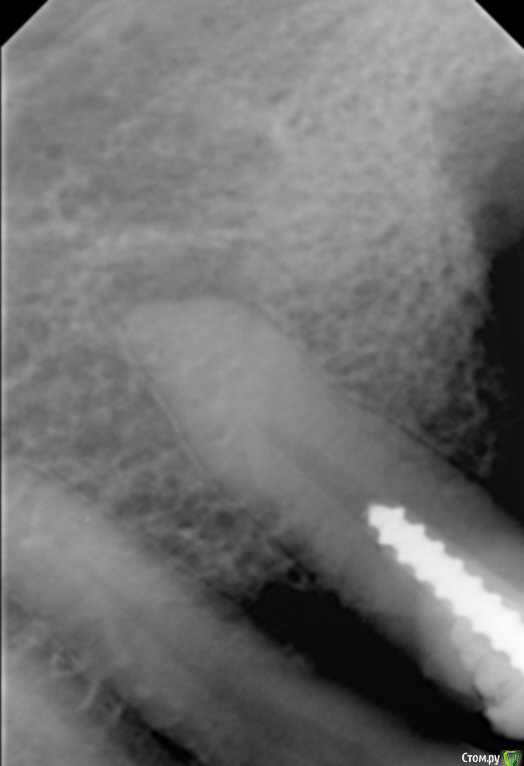

Елена509 Опубликовано 19 ноября, 2015 Поделиться Опубликовано 19 ноября, 2015 Доктора, помогите, пжл, ситуация какая - ортопед направил для удаления штифта и перепломбирования к.к 35, начали - анестезия, выудили штифт, начали расширять, уперлись на 15 мм, пошли на снимок с гутт штифтом(прилагается), недолет, вернулись, сразу прошли дальше, по апексу -18мм, убавила до 17,5, мастер штифт - 35, латералка, пошли на контроль, а там - загнутый штифт за верхушкой(рг прилагается), вернулись, все вытащила, загнутый тоже(95% - я его прям признала), отмыли просушили, по апексу те же 18мм, примеряю мастер штифты все как то не так встает, в итоге 70 подогнала, на те же 17,5 мм, поставила, с латералкой, идем на контроль, там вот такая вот фигня(рг - "последний"), вопросы - это что, невытащеннный гут.штифт или на его место эпоксидка затекла? что с прогнозом и что делать? 1 Ссылка на комментарий

Сева северный Опубликовано 19 ноября, 2015 Поделиться Опубликовано 19 ноября, 2015 (изменено) перед тем, как пошли делать с гут.штифтом рг недолет показывал, вроде нормально все было, когда пломбировали, штифты тоже никуда не уходили на месте стояли, я даже как то растерялась сильно, когда на контрольном на столько за апекс ушлисудя по фото....зуб резарцинен..... с дефектом твердых тканей( это диазноз)..ферол наверное отсутствует. Чтобы было понятно ......лечение резарциненого зуба с таким разрушением..+ осложненным необходимостью эндолечения .... является альтернативой удалению.Что касается :Что за верхушкой ?.... Границы четкие, если вынули гуту ....крючком.... для себя считайте силер..даже если и гута связь с каналом зуба отсутствует. поэтому реакция будет либо незначительная , либо отсутствовать вообще. Прогноз по зубу, строил бы из ортопедической целесообразности.... Изменено 19 ноября, 2015 пользователем Сева северный 1 Ссылка на комментарий

Л Ю С Я Опубликовано 20 ноября, 2015 Поделиться Опубликовано 20 ноября, 2015 Здесь явная резорбция апекса, поэтому локатор мог показывать неправильно. В таких случаях делайте снимок с финишным файлом, где он? Ориентируйтесь больше на рентгенологическую длину, после лечения может произойти ещё небольшая убыль апекса, поэтому пакуйте -0,5, лучше мта. Какой билдап планируется в зубе? И вообще надо рассматривать картину восстановления окклюзии в целом 1 Ссылка на комментарий

Сева северный Опубликовано 20 ноября, 2015 Поделиться Опубликовано 20 ноября, 2015 лечение таких зубов лучше начинать с диагностического КТ ... Согласен ... с колегой , что здесь возможна резорбция ... но поставить ее можно только по серии ваших снимков. Первый снимок не давал четкой картины.А теперь подумайте как вы поступили , зная это перед лечением. Ссылка на комментарий